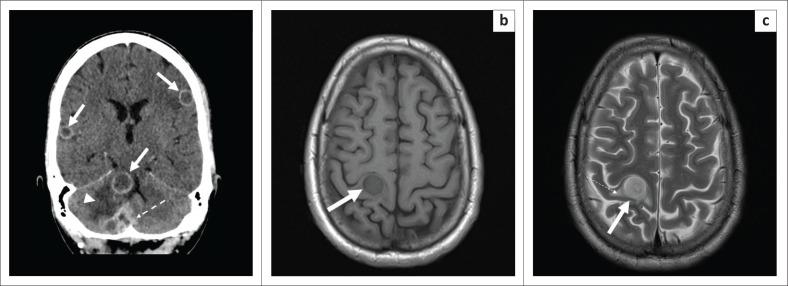

Extra-pulmonary tuberculosis (EPTB), caused by , is the leading cause of communicable disease-related deaths in people with human immunodeficiency virus (HIV) worldwide and in South Africa. disseminates haematogenously from an active primary lung focus and may affect extra-pulmonary sites in up to 15% of patients. Extra-pulmonary TB may present with a normal chest radiograph, which often causes a significant diagnostic dilemma. This review describes the main sites of involvement in EPTB, which is illustrated by local imaging examples.

由……引起的肺外结核病(EPTB)是全球和南非人类免疫缺陷病毒(HIV)感染者中与传染病相关死亡的主要原因。……从活跃的原发性肺部病灶经血行播散,高达15%的患者可能累及肺外部位。肺外结核病可能胸部X线片表现正常,这常常造成重大的诊断困境。本综述描述了肺外结核病的主要受累部位,并通过局部影像学实例进行说明。 (注:原文中“caused by ”和“disseminates haematogenously from an active primary lung focus and may affect extra-pulmonary sites in up to 15% of patients.”前缺失关键信息)